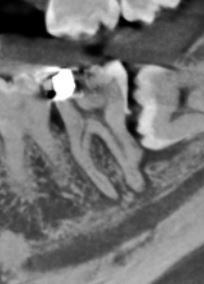

The LL8 is unerupted and horizontally impacted against the LL7 with the mesial root apex touching

the IDC. The tooth has a normal follicle space with no erosion of the adjacent distal root.

The LL7 displays distal calculus and severe loss of periodontal bone attachment. There is mesial horn

pulpal exposure with apical radiolucencies 1-2 mm wide.